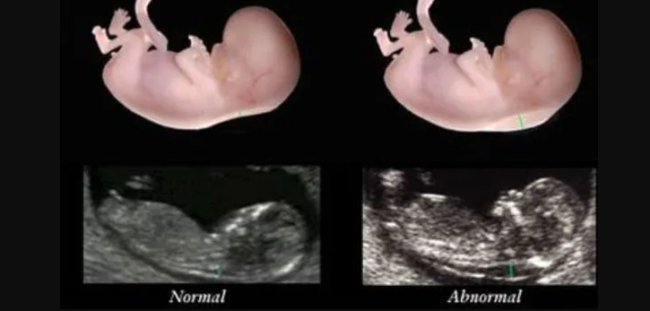

Erken doğum olarak ifade edilen preterm doğum, yeni doğan bakım ünitelerinde gelişmelere rağmen doğuştan anomalisi olmayan yeni doğan bebeklerde ölüm ve sakatlığın önde gelen nedenlerinden biridir. Erken doğum yenidoğan ölümlerinin yaklaşık %75’inden sorumludur. Erken doğan bebeklerde pek çok organ, özellikle akciğerler gelişimini tamamlamamış olduğundan yeni doğan bakım ünitesi desteği gerekli olmaktadır. Erken doğum ne yazık…